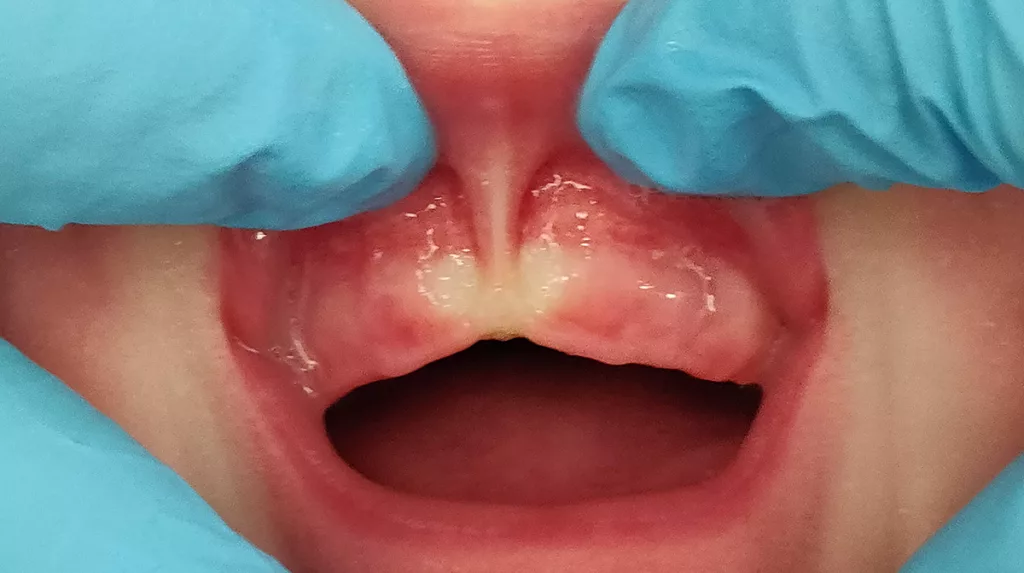

5. Ein Blanchieren (Blanching), also die Weißfärbung des Zahnfleisches am Ansatzpunkt ohne eine Funktionseinschränkung der Oberlippe, ist ein Faktor und kein allein entscheidender Grund, eine sublabiale Faszienplastik zur Optimierung des Stillens zu empfehlen, weil ein Blanchieren auch bei ausreichend guter Lippenfunktion auftreten kann (Abb. 1).

6. Eine Einkerbung (Notch) inmitten der Zahnleiste am Ansatzpunkt des Lippenbandes ist kein Hinweis dafür, dass dadurch das Stillen behindert wird (Abb. 2). Allerdings kann eine Einkerbung ein Hinweis dafür sein, dass die Kauleiste durch das Lippenband in der Entwicklung beeinträchtigt und deformiert wird (Abb. 3) und die Wahrscheinlichkeit für eine Lückenbildung bei den Frontzähnen erhöht sein könnte. Ein wissenschaftlicher Nachweis für diese Annahme fehlt noch. Heo [5] berichtet in einer Fallstudie von einer starken Verkürzung des Oberlippenbandes, die eine Hypoplasie des Prämaxillarbereichs, eine abnorme Lippenbewegung und -kontur bei einem Kind zeigt. Es bestand eine knöcherne anteriore Alveolarhypoplasie mit tiefem Sulkus im vorderen Oberkiefer, die mit einer 3D-Aufnahme mittels Computertomographie dokumentiert wurde. Ein postoperatives dreidimensionales CT-Bild des Gesichts, 10 Monate nach Frenotomie, zeigt ein gut knöchernes Wachstum von Prämaxilla und Alveole im Vergleich zum präoperativen CT-Status [5].